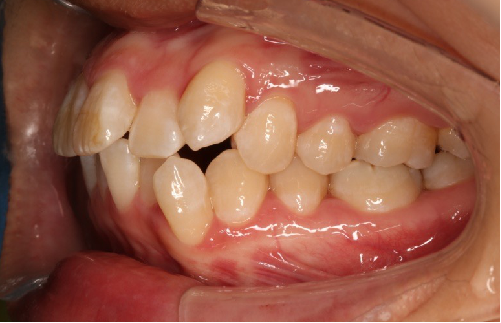

2018.11.14  术后侧面改善明显,露龈笑改善明显,笑弧笑线协调,颏部肌肉紧张度明显改善

2018.11.14  术后磨牙尖牙I类关系,中线齐,覆合,覆盖正常

2019.08.06  术后  10个月复查

宏观评价:面部对称,面下三分一比例协调,上下唇凸度正常,上颌牙列内收转矩控制良好,下颌后缩改善,颏唇沟变得更加柔和,术后达到基本直面型。

迷你观评价:上下牙齿中线与面中线对齐,笑弧协调,微笑时牙龈暴露量正常,微笑时横向正常,左右唇基本对称。

微观评价:牙齿整齐,咬合关系良好,上下前牙转矩及突度控制良好,磨牙关系I类,尖窝咬合关系良好,OB,OJ正常。